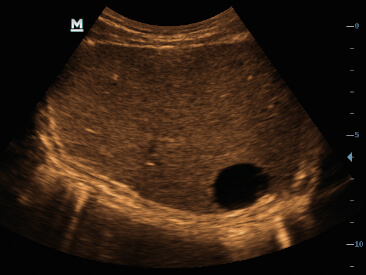

Clinical Images